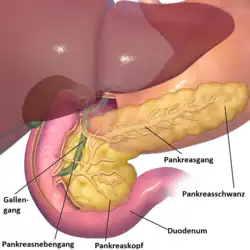

Anatomie

Die Bauchspeicheldrüse ist eine 40 bis 120 g schwere Drüse im Retroperitoneum, hinter dem Magen, links vom Zwölffingerdarm und wird in einen Kopf, einen Körper und einen Schwanz untergliedert. Der Schwanz berührt links Milz und Niere. Der Hauptgallengang durchquert rechts den Kopf der Bauchspeicheldrüse. Die Aorta und mehrere große Eingeweidearterien (Truncus coeliacus, obere Mesenterialarterie, Milzarterie) haben engen Kontakt zur Bauchspeicheldrüse, ebenso die untere Hohlvene und die Pfortader.[10] Alle diese Strukturen können von Bauchspeicheldrüsenkrebs erfasst werden. Die Ausführungsgänge für das Bauchspeicheldrüsensekret (Wirsung- und der beim Menschen nur selten vorkommende Santorini-Gang) verlaufen durch das ganze Organ und können vom Tumor verstopft werden. Ihre Blutversorgung erhält die Bauchspeicheldrüse aus dem Truncus coeliacus und der oberen Mesenterialarterie, manchmal auch aus einer abweichenden Leberarterie, was Operationen erheblich erschweren kann. Das verbrauchte Blut fließt in die obere Mesenterialvene und in die Milzvene ab. Die Lymphe strömt in alle Richtungen zu den nächstgelegenen Lymphknotengruppen (Bauchspeicheldrüsen-, obere und untere Bauchspeicheldrüsen-Zwölffingerdarm-, Leber-, Zölikial-, obere Mesenterial-, Milzlymphknoten und obere paraaortale Lymphknoten), die alle von einer Metastasierung betroffen sein können.[11]

Die Bauchspeicheldrüse ist überwiegend exokrin („nach außen ausscheidend“): Ihr Verdauungssekret wird über die beiden Ausführungsgänge in den Zwölffingerdarm abgegeben. Sie enthält aber auch endokrine („nach innen ausscheidende“) Zellgruppen in den sogenannten Langerhans-Inseln, die die Hormone (unter anderen Insulin und Glucagon) produzieren und an das Blut abgeben. Beide Gewebe können prinzipiell Tumoren entwickeln. Über 95 % der Pankreastumoren entstehen aus dem exokrinen Organ, genauer gesagt aus dem Gangepithel und den Azinuszellen.[12] Neben den meist gutartigen serös-zystischen Neoplasien (SCN, früher „seröse Zystadenome“) sind es vor allem Karzinome. Tumoren des endokrinen Pankreasgewebes kommen dagegen fast nur bei erblichen Syndromen vor. Sie werden zu den neuroendokrinen Tumoren gerechnet.

Drei Viertel der Tumoren entstehen im Pankreaskopf, dem am weitesten rechts, am Zwölffingerdarm gelegenen Anteil. 20 % der Tumoren treten im mittleren Anteil (Corpus) und fünf Prozent im linksseitigen Pankreasschwanz auf.